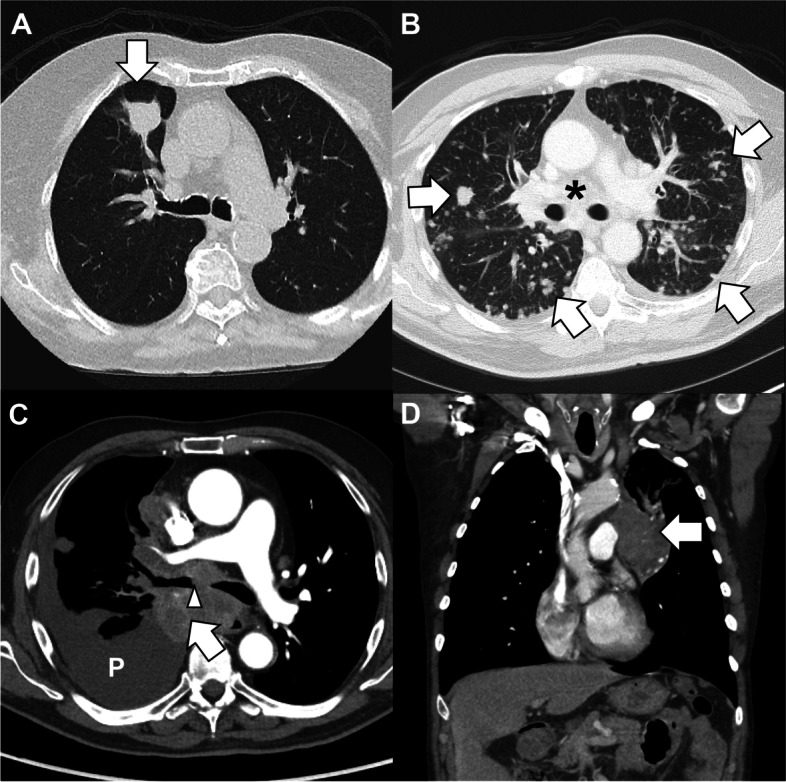

Findings: Lung cancer, encompassing 10-12% of cancer-related emergency department visits and a 66% admission rate, is the most fatal malignancy in both men and women. Most patients presenting to the ED have not seen a primary care provider or undergone screening. Ultimately, half of those with a new lung cancer diagnosis in the ED die within 1 year. Incidental findings on computed tomography are mostly benign, but emergency staff must be aware of the factors that make them high risk. Radiologic presentations range from asymptomatic nodules to diffuse metastatic lesions with predominately pulmonary symptoms, and some may present with extra-thoracic manifestations including neurologic. The short-term prognosis for ED lung cancer patients is worse than that of other malignancies. Screening offers new hope through earlier diagnosis but is underutilized which may be due to racial and socioeconomic disparities. New treatments provide optimism but lead to new complications, some long-term. Multidisciplinary care is essential, and emergency medicine is responsible for the disposition of patients to the appropriate specialists at inpatient and outpatient centers.